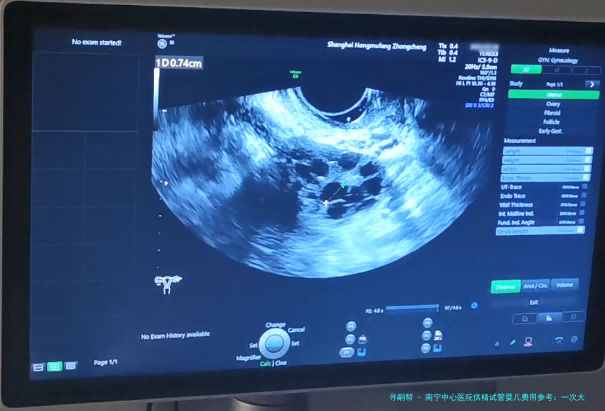

在超声引导下,通过微穿刺方式取出成熟的卵子。 4.